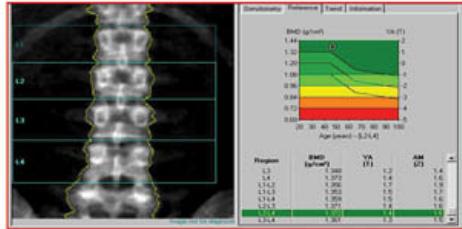

DEXA Scan

Overview

- Bone Mineral Density (BMD) measurement

- DEXA: Dual Energy X-ray Absorptiometry

- Primary sites: Spine / neck of femur

WHO Classification of BMD Using DEXA Scan

Reference: L2-L4 vertebrae

| Category | T-Score | Description |

|---|---|---|

| Normal | Within 1 SD of young adult mean | |

| Osteopenia | -1 to -2.5 | Between 1-2.5 SD below young adult mean |

| Osteoporosis | More than 2.5 SD below young adult mean | |

| Severe Osteoporosis | + fracture | Osteoporosis with history of fracture |

Note: T-score represents the number of standard deviations (SD) a patient is above or below the mean BMD of a young adult.